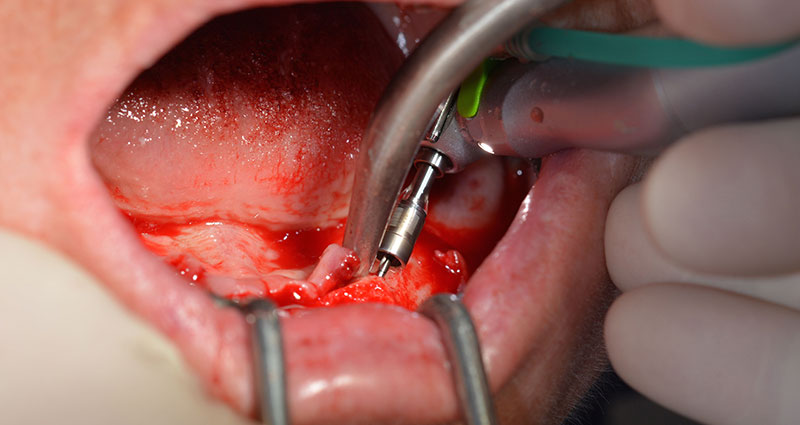

After removal of the residual dentition in the mandible, the alveolar crest was exposed from 37 to 47.

The mental foramen was first identified as a limiting anatomical structure and then the cortical bone of the crest was smoothed with the straight handpiece and a large rose-head bur (Fig. 4).

residual dentition

Fig. 4